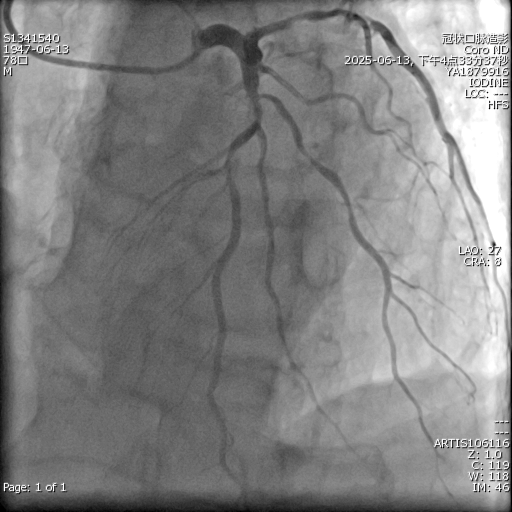

心内科团队积极抗心衰治疗,冠脉造影显示:患者心脏三支主要血管均严重狭窄病变,且伴有严重钙化。若不及时干预,患者随时面临心源性猝死的危险。然而,传统介入治疗风险极高,单纯药物治疗难以改善预后,救治面临巨大挑战。